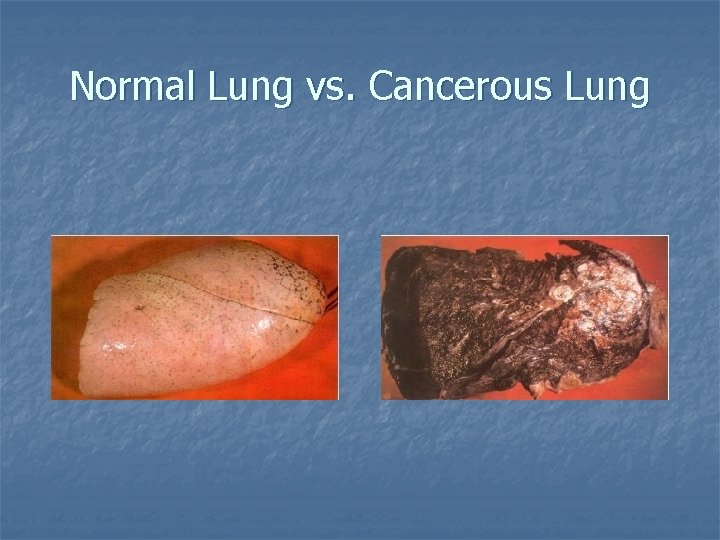

Normal Lung vs. Cancerous Lung